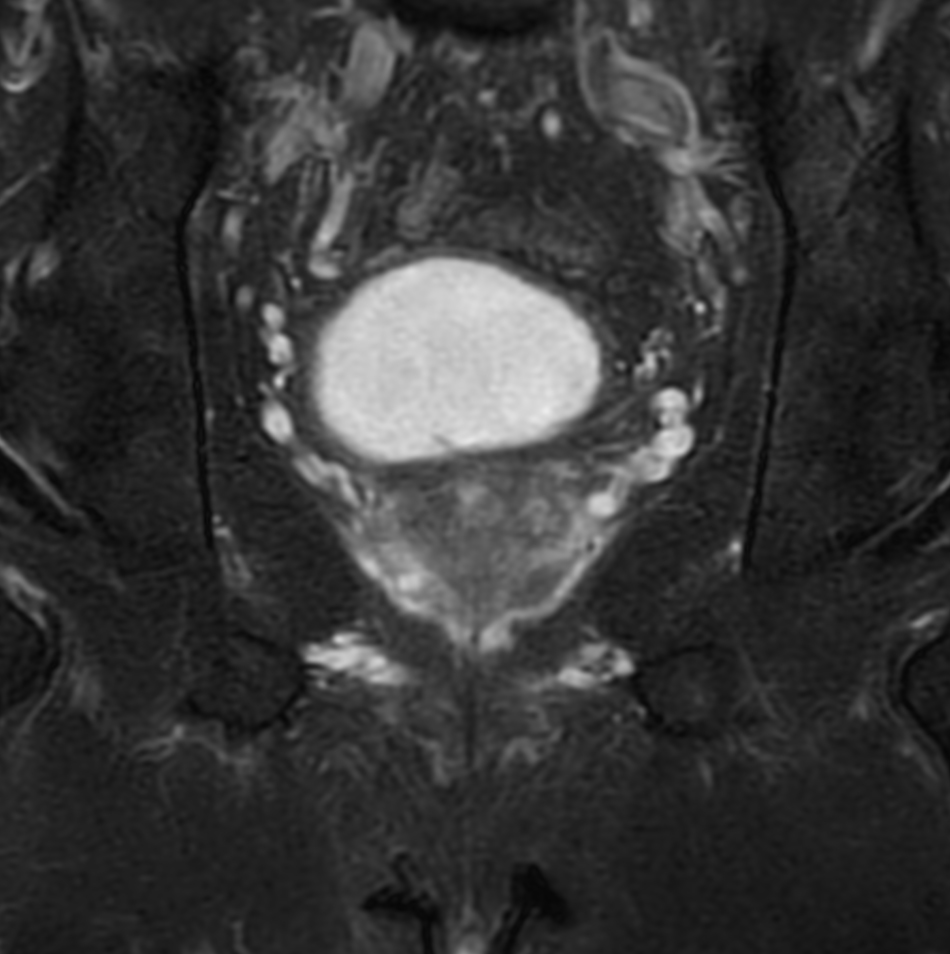

Prostate lesion with fat-free mDIXON XD imaging

Seirei Mikatahara General Hospital, Japan